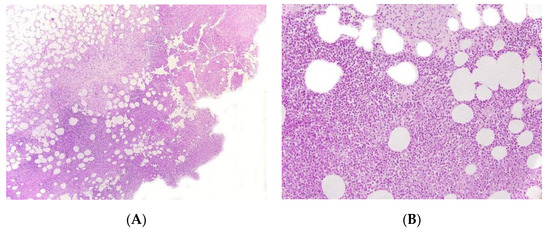

2.4. Autoinflammatory Diseases

Early-onset panniculitis with systemic inflammation had been reported in cases of autoinflammatory diseases with or without an associated immunodeficiency [13,14]. Most cases have variable, non-specific histopathologic features: lobular or septal panniculitis with a mixture of cells or with a predominance of neutrophils or lymphocytes (Figure 3 and Figure 4). However, the histopathologic features can sometimes have diagnostic value, such as the granulomatous infiltrate characteristic of Blau syndrome (BS) or the polyarteritis-nodosa-like vasculitis in deficiency of adenosine deaminase 2 (DADA2). The presence of early-onset panniculitis with systemic inflammation should prompt the physician to screen for autoinflammatory disorders.

Figure 4.

Panniculitis associated with inherited immunodeficiency. (A) Lobular panniculitis with dense neutrophilic infiltrate replacing part of the subcutis (original magnification ×80). (B) Closer view of showing entrapped adipocytes within the neutrophilic infiltrate (original magnification ×200).